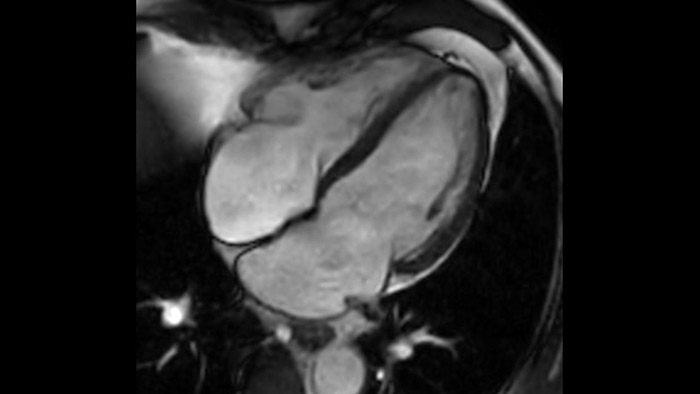

A utilidade do diagnóstico e prognóstico da RM cardíaca está a aumentar. Avalie a anatomia e função do coração utilizando aquisições cine, adquira informações sobre a perfusão e viabilidade do tecido cardíaco, visualize potenciais edemas com sequência de sangue escuro, aceda e quantifique mesmo a caracterização do tecido com a CardiacQuant.

O IntelliSpace Portal oferece um abrangente conjunto de RM cardíaca, fornecendo fluxos de trabalho dedicados para análise funcional, viabilidade, LGE, avaliação do mapeamento cardíaco e análise funcional do VD/VE em menos de 5 min. por caso3.